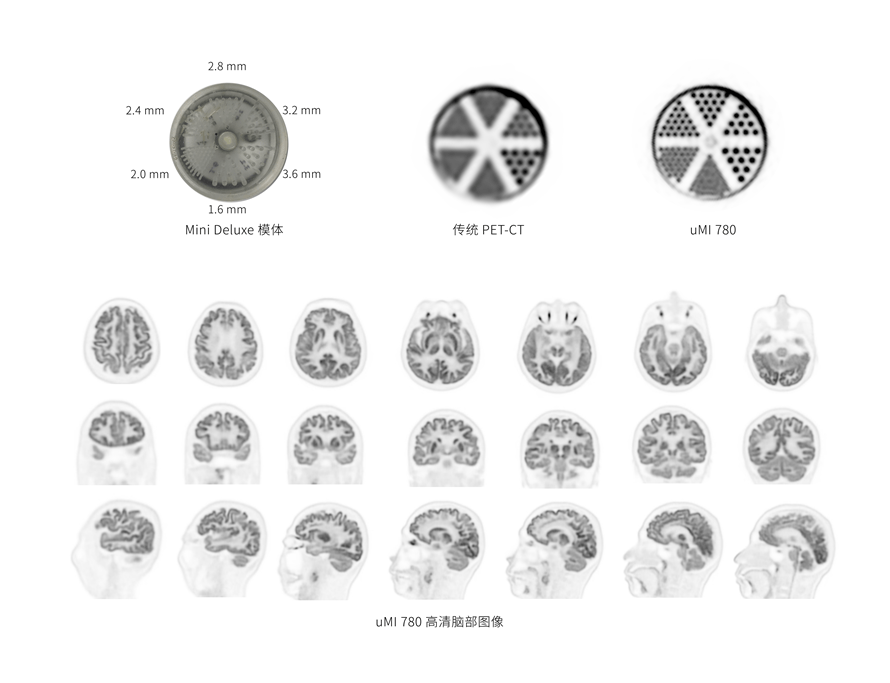

2.9mm

超清NEMA分辨率成像